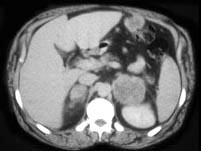

问题 男,56岁,有恶性黑色素瘤病史,请结合图像,作出诊断 ( )

选项 A、肾上腺转移瘤 B、肾上腺嗜铬细胞瘤 C、肾上腺髓样脂肪瘤 D、肾上腺癌 E、肾上腺腺瘤

答案 A